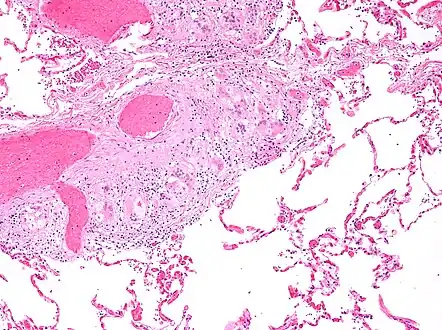

Histopathology

Sarcoidosis is characterized by the formation of non-necrotizing ("non-caseating") granulomas in various organs and tissues.[96] Giant cells, specifically Langhans giant cells, are often seen in sarcoidosis.[97] Schaumann bodies seen in sarcoidosis are calcium and protein inclusions inside of giant cells as part of a granuloma.[98] Asteroid bodies can be seen in sarcoidosis.[98] Hamazaki–Wesenberg bodies can be seen in lymph nodes and more rarely in lung biopsies with sarcoidosis and are inclusion bodies of lysosomes with protein, glycoprotein and iron.[99]